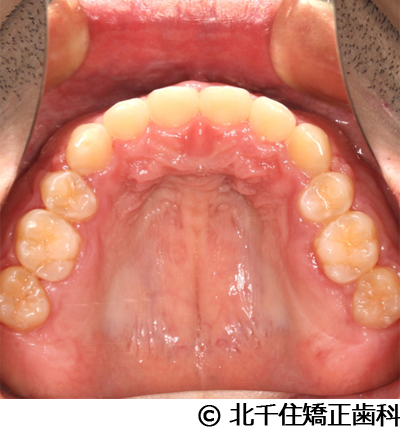

【症例5】上顎前突

- 治療前

- 治療後

- 治療名

- 上顎前突

- 費用

- 1,263,600円(税込)

- 期間

- 2年8ヵ月

- 治療回数

- 32回

- 通院頻度

- 1ヵ月ごと

- 年齢

- 13歳3ヵ月(初診時)

治療内容

-

患者様の症状

主訴:出っ歯

治療方法

骨格性の上顎前突、ヘッドギアを併用して上下顎第一小臼歯4本抜歯してワイヤー矯正。

治療結果

骨格性上顎前突に対し、ヘッドギアおよび抜歯を併用した矯正治療により歯列および咬合関係の調整を行った症例である。

治療後は保定装置を使用し、歯列および咬合の安定維持を目的として定期的な経過観察を行っている。